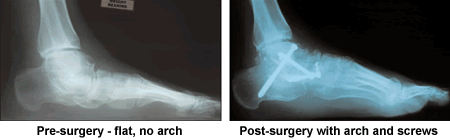

I first started seeing doctors about my feet when I was 5 years old. I was diagnosed with flat feet and a few years later was fitted for orthotics, which I have been wearing until I met Dr. Leavitt. I have always been very active in athletics playing all sports thru high school and soccer thru college. I stayed very active after college with activities including soccer, tennis, golf, and running. My "flat feet" were a continued source of pain after my daily activities and each morning it took several steps and stretching to get my feet to function.

As the years progressed and I moved into my thirties I noticed that my feet were starting to deform creating additional discomfort. I continued to stay active but had to moderate some of my activities because of my feet. With the change in my feet I started to see podiatrists, they diagnosed severe flat feet and put me into rigid orthotics, had me wear hiking boots for added support and suggested I might want to consider other activities. Having a family history of high cholesterol and heart problems my activities and running workouts were a fixed part of my health regimen and I visited other podiatrists to see if there was anything to be done. Only one suggested surgery as a last resort and one told me my feet were the second worst he had seen in his practice.

As I turned fifty I had to minimize the time I spent on my feet and eliminate running, as my feet would not support me for any length of time and the deformities continued to worsen. In June of 2003 I ruptured a tendon in my right foot kicking a soccer ball. At the time I did not see a doctor. I lived with the additional pain and my foot would slap down when I walked. My wife encouraged me to see a doctor, but since none had been able to offer much hope for my feet, I chose to live with my feet as they were.

I had surgery on my other foot four months later. Today a little less than two years from my first surgery, I have been able to return to all my former activities including running, skiing and tennis. Each day my feet are still strengthening and improving and I have no pain in my feet and look forward to each day with no restrictions on what I do because of them. Finding Dr Leavitt gave me a new lease on life. Instead of dreading putting my feet down on the floor in the morning, I now look forward to getting up and enjoying the day.